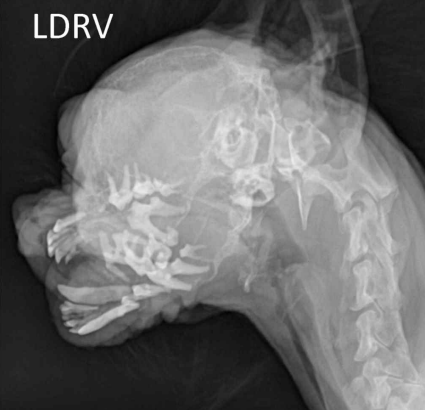

• 방사선 검사

하악 뼈 소실, 이빨 소실, 척추 뼈 밀도 감소,

Renal osteodystrophy

(신성 골이형성)

- 뼈에서 칼슘이 과도하게 빠져나와 골밀도 감소

- 성장기(6-12개월) → 오히려 뼈 두꺼워질 수 있음

- 노령, CKD → Rubber jaw : 코가 고무처럼 물렁해짐

- 상악, 하악, 치주골에서 칼슘 감소, 뼈 밀도 감소